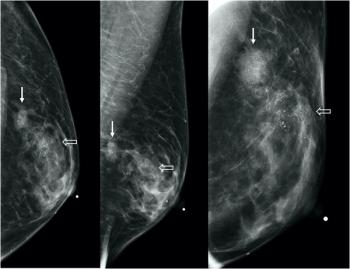

A nuanced approach is needed to weigh the risk of vaccination-associated axillary lymphadenopathy against the risk of delaying breast cancer screening.